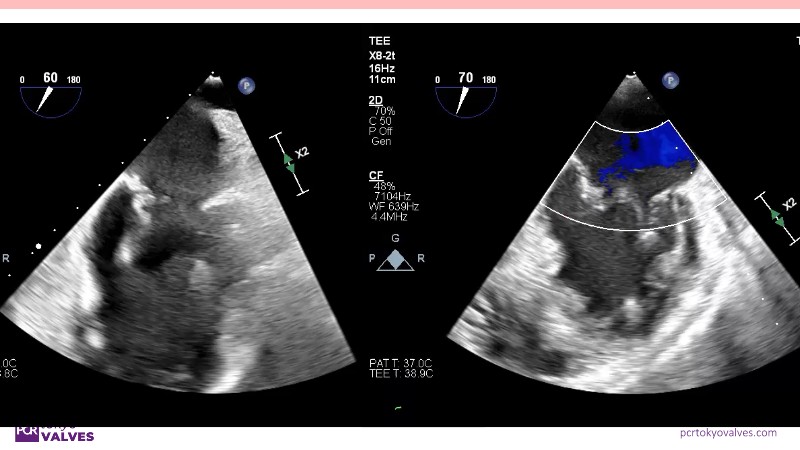

Explore the latest advancements in TEER therapy with this PCR Tokyo Valves 2025 session dedicated to MitraClip. Through expert-led case discussions, gain a deeper understanding of complex scenarios, including restricted posterior leaflet in functional mitral regurgitation, commissure lesion (A3P3), and MitraClip combined with Amulet.

This session also highlights key findings from the OCEAN study, shedding light on 1-year heart failure rehospitalisation outcomes with MitraClip. Additionally, discover how atrioventricular valve morphology impacts treatment strategies and how the four available clip sizes can be used to personalise and optimise TEER outcomes.